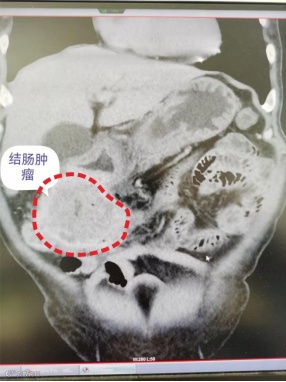

入院后,北海市第二人民医院为林先生完善了上下腹CT平扫+增强检查,结果让所有人都绷紧了神经:结肠肝区至横结肠近端、胃窦部位存在占位性病变,高度怀疑为结肠癌,且已侵犯胃窦;同时还伴有升结肠-结肠肝区及阑尾炎性改变、乙状结肠异常强化灶、腹腔盆腔少量积液、主胰管扩张等问题。

影像显示肿瘤